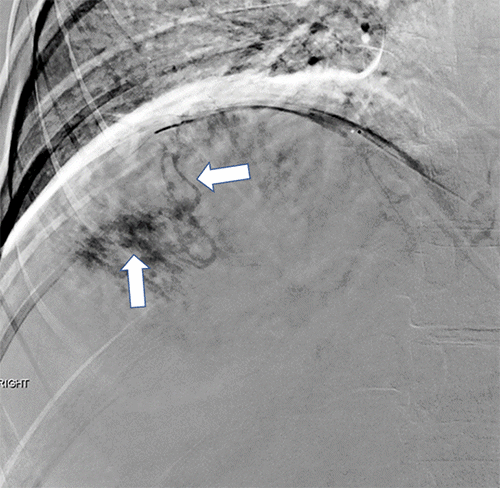

In anticipation of significant intraoperative bleeding during resection of the massive hemangioma, the patient underwent preoperative angioembolization the day prior to surgery. Hepatic angiography identified the hemangioma’s arterial supply: the right inferior phrenic artery (Figure 2) and three secondary branches of the right hepatic artery (Figure 3). All four vessels were successfully embolized with Gelfoam slurry. The procedure was well-tolerated, and no complications were reported either during the procedure or in the post-embolization period. The patient then proceeded to surgical resection of the hemangioma the following day.

Figure 2. Preoperative Angiography Demonstrates Hemangioma Blood Supply. Published with Permission

Selective angiography of a branch of the right inferior phrenic artery shows opacification, followed by subsequent filling of the hemangioma, confirming arterial supply